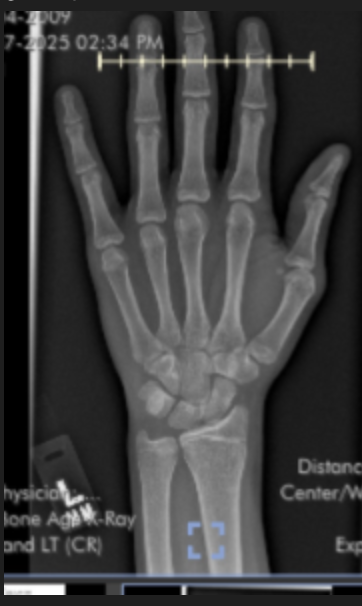

Doctors told me based on wrist xray+ bone age I had 1-2 cms max more

In my opinion wrist xrays are completly inaccurate to see how much growth is left, your bone age will give you some idea, but there are much better methods